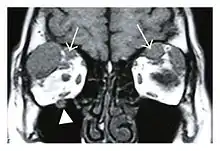

The extent of inflammation that can occur in IgG4-ROD is well demonstrated on magnetic resonance imaging (MRI).

Infraorbital nerve enlargement (IONE) is considered to be a particularly suspicious sign of IgG4-ROD, but seems to occur only when inflammation is in direct contact with the infraorbital canal.[10] IONE is defined as the infraorbital nerve diameter being greater than the optic nerve diameter in the coronal plane.

![]() Bilateral supraorbital nerve enlargements (arrows) and right infraorbital nerve (arrow head) enlargement in a 47-year-old woman with a serum IgG4 of 1000 mg/dL.[1] (T1-weighted MRI) |